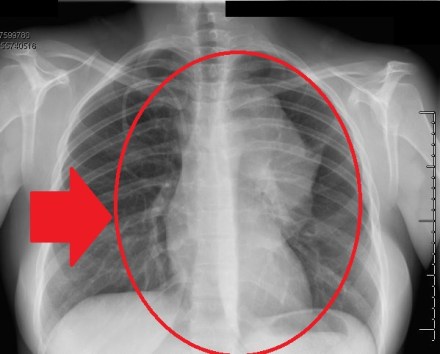

And she came back in to the exam room faster than I have ever seen a doctor return after tests. Her face was very still, but her eyes were very shiny and sharp. She smiled, and it was stiff. I was confused as she held up the X-ray to show me a large cloudy spot, larger than my entire hand, showing across my chest.

She reassured me it might be nothing, but she also told me I had to go get a CT scan. I asked when that would be scheduled – sometime during the next week? With her smile still frozen on her face, she told me she’d already scheduled it, and I had to go to the imaging lab down the road right now. Not that there was anything to worry about or anything. I just had to go. Now. And after the CT scan was done, I would need to come back.